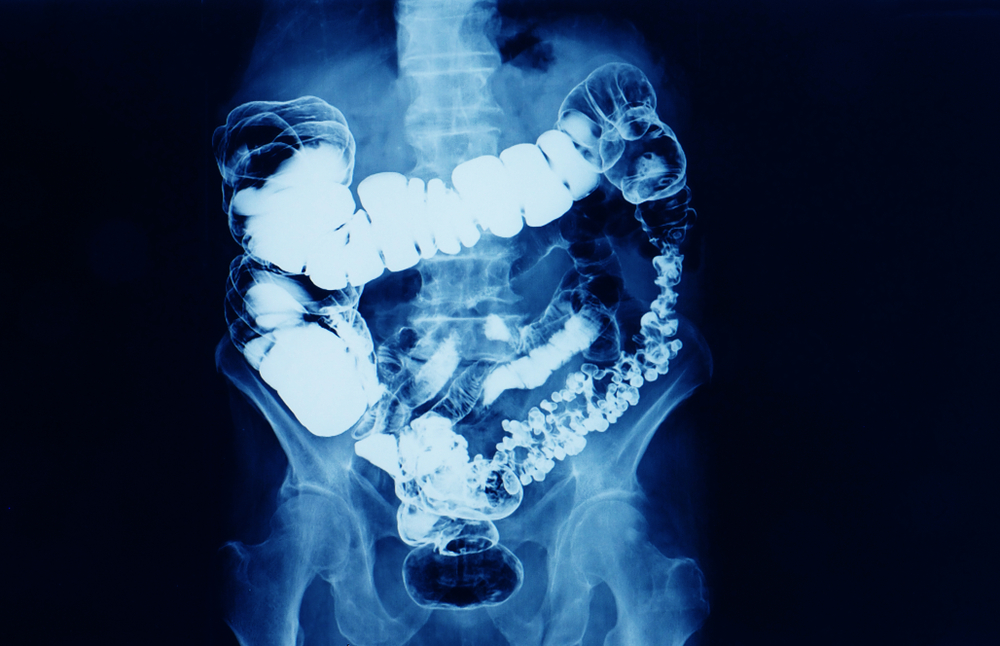

Barium Enema

What is a Barium Enema? A barium enema, also called a lower gastrointestinal (GI) series, is a diagnostic test used to evaluate the colon and rectum for abnormalities. During the procedure, liquid barium sulfate (a contrast dye) is introduced into the colon through the rectum. The barium coats the lining of the intestine, allowing it […]